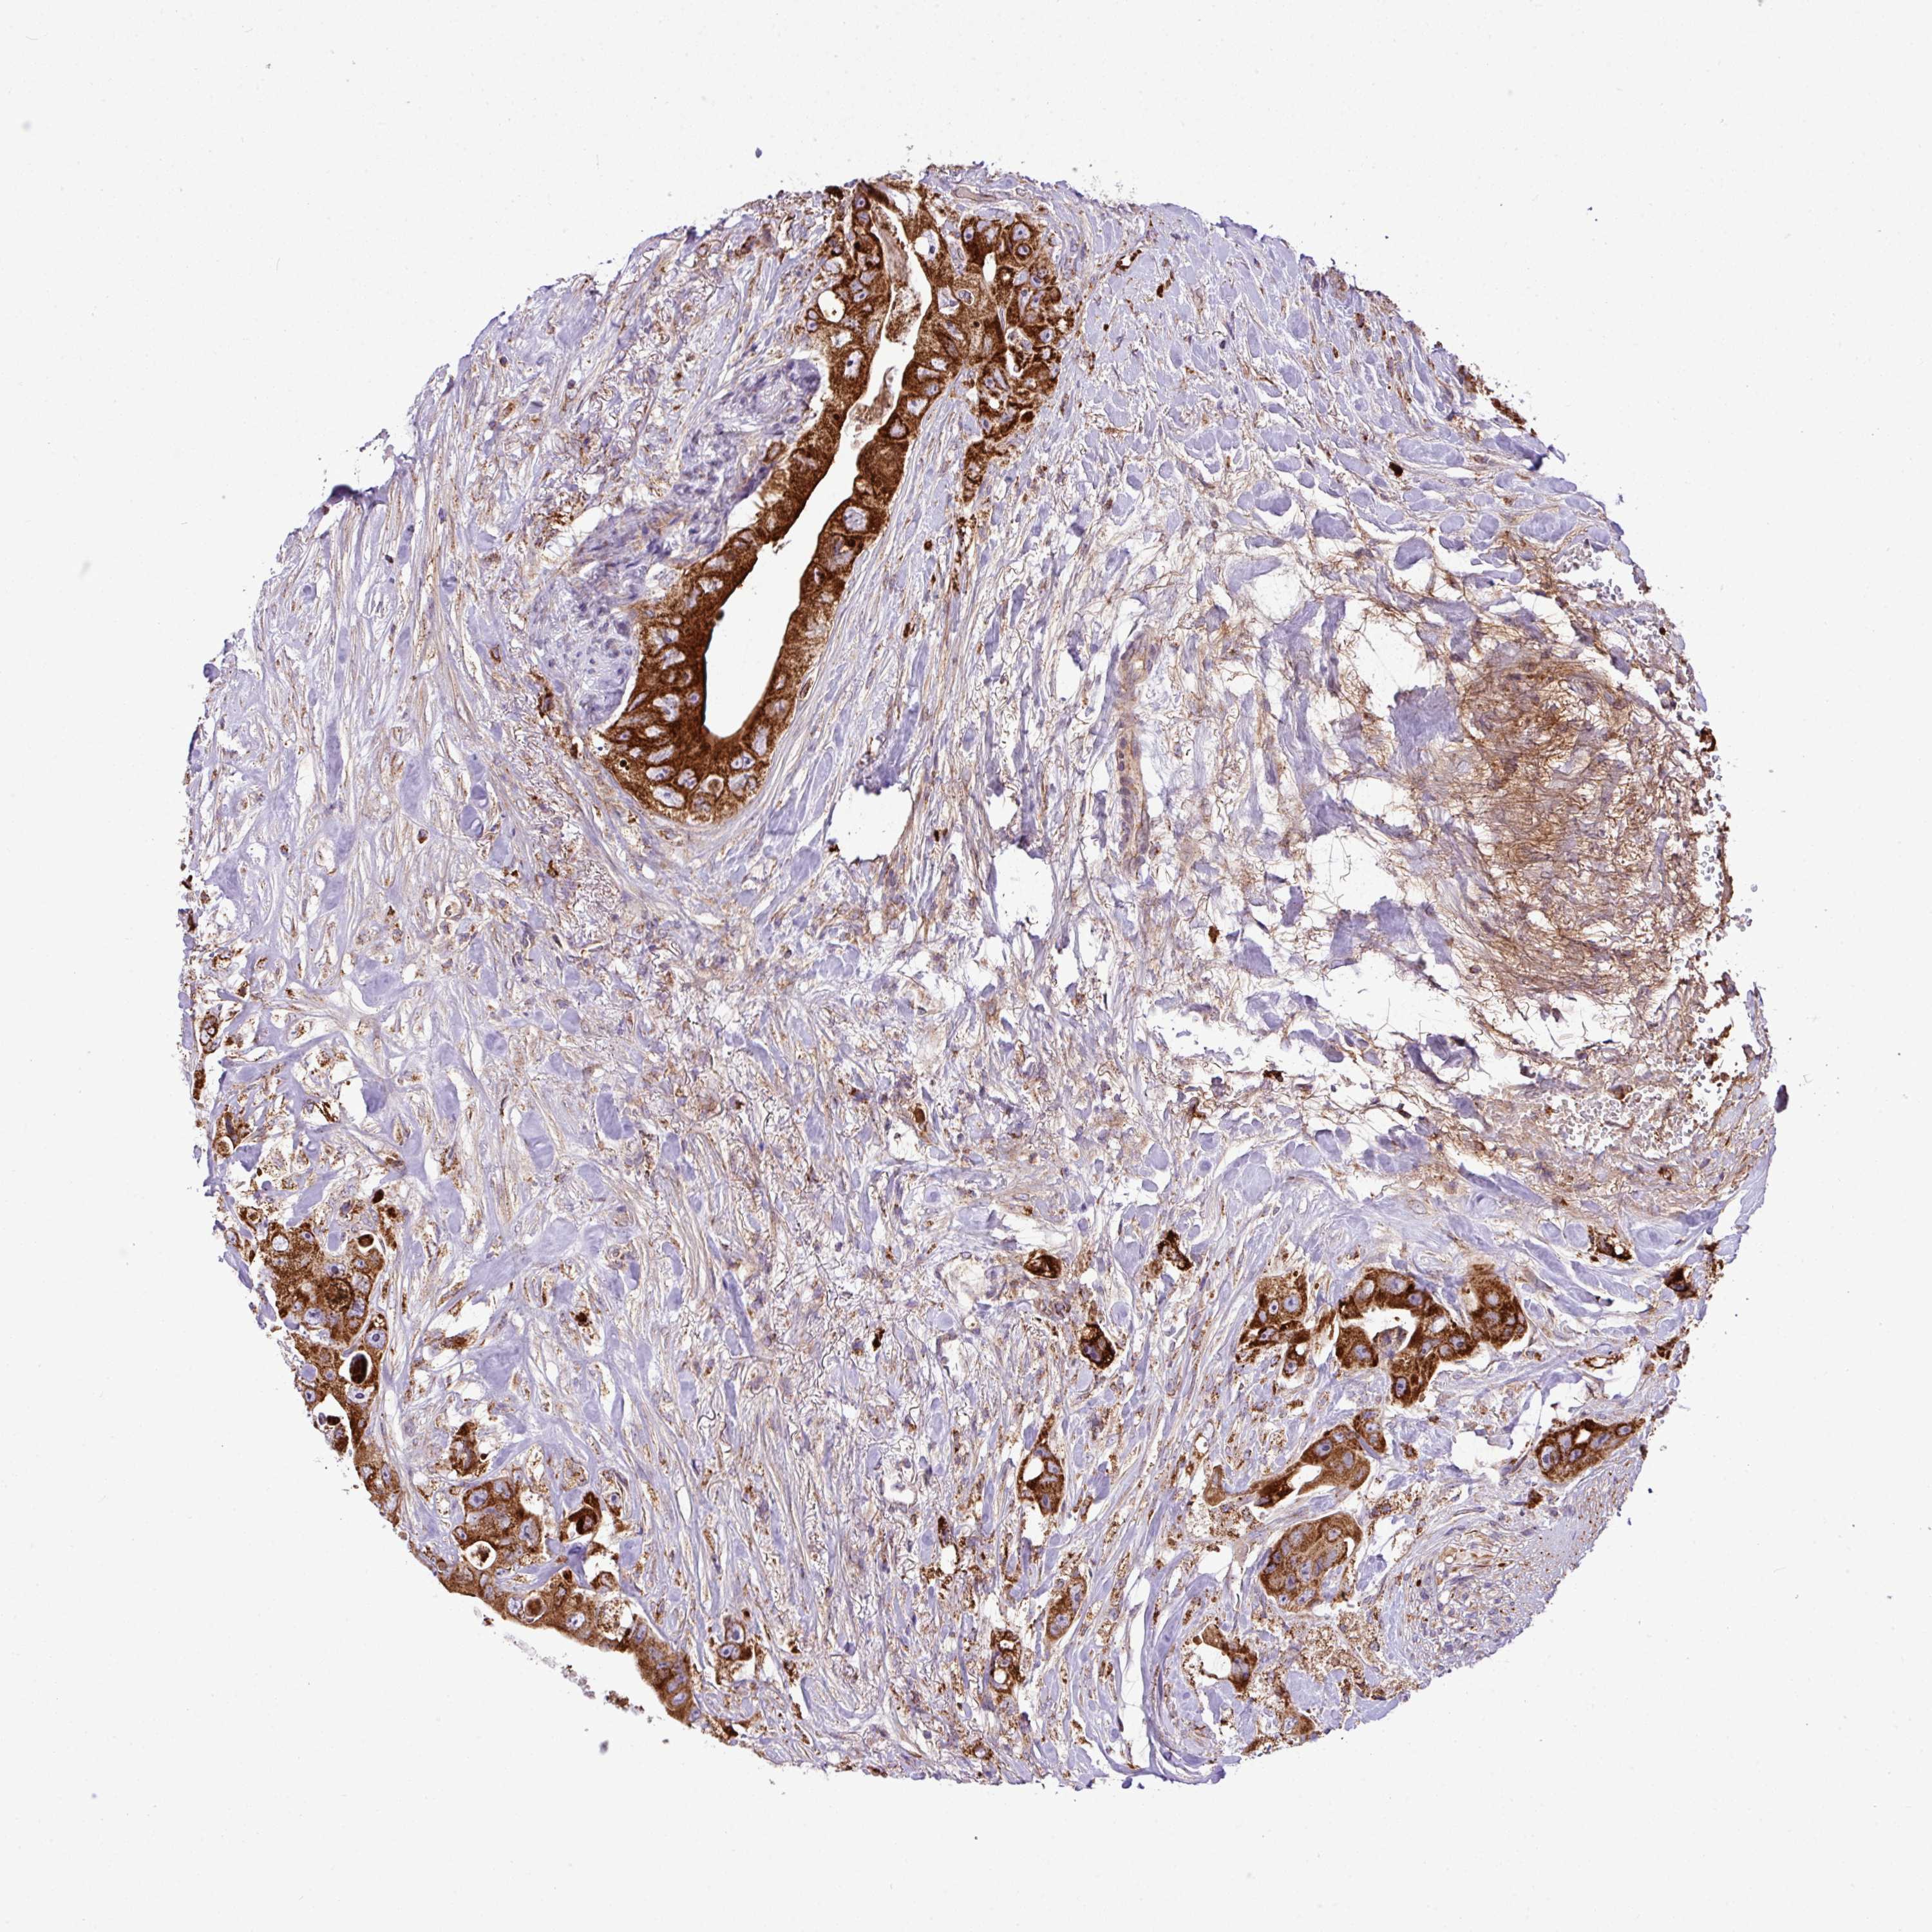

CANCER COLORECTAL CANCER Show tissue menu

Colorectal cancer

Human cancer

Colon adenocarcinoma